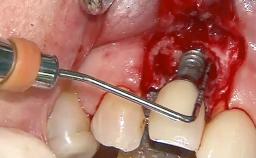

Surgical Management of Peri-Implantitis: Reconstructive Surgical Treatment with Three-Year Follow-up After Treatment

A 70-year-old female patient was referred by her general dentist to the periodontist for assessment and management of an infection associated with implant 36. The general dentist had noted suppuration on probing during examination.